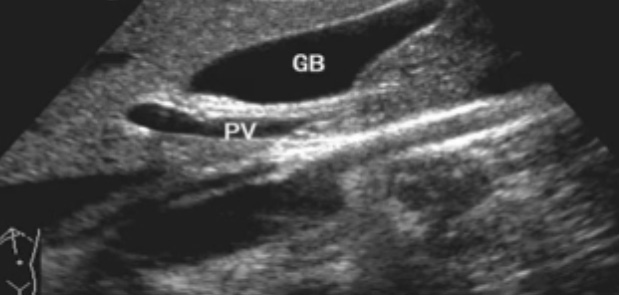

二、正常膽管超聲圖像

肝內(nèi)膽管-無膽管擴(kuò)張的情況下,超聲一般只能顯示膽管的一、二級支,不能顯示二級以上的肝內(nèi)膽管肝外膽管(聲像圖上大致分為兩段)上段與門靜脈伴行,位于門靜脈主干的右前方;下段與下腔靜脈伴行并延伸進(jìn)入胰頭背外側(cè)。膽道、肝動脈與門靜脈的關(guān)系。